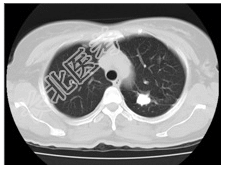

- [材料题] 患者,女性,51岁。体检发现左上肺高密度结节。查体:双肺呼吸音清,未闻及干湿性啰音。心脏无异常。行胸部CT平扫。

- 简答题1、患者的诊断及依据是什么?

- 简答题2、鉴别诊断有哪些?